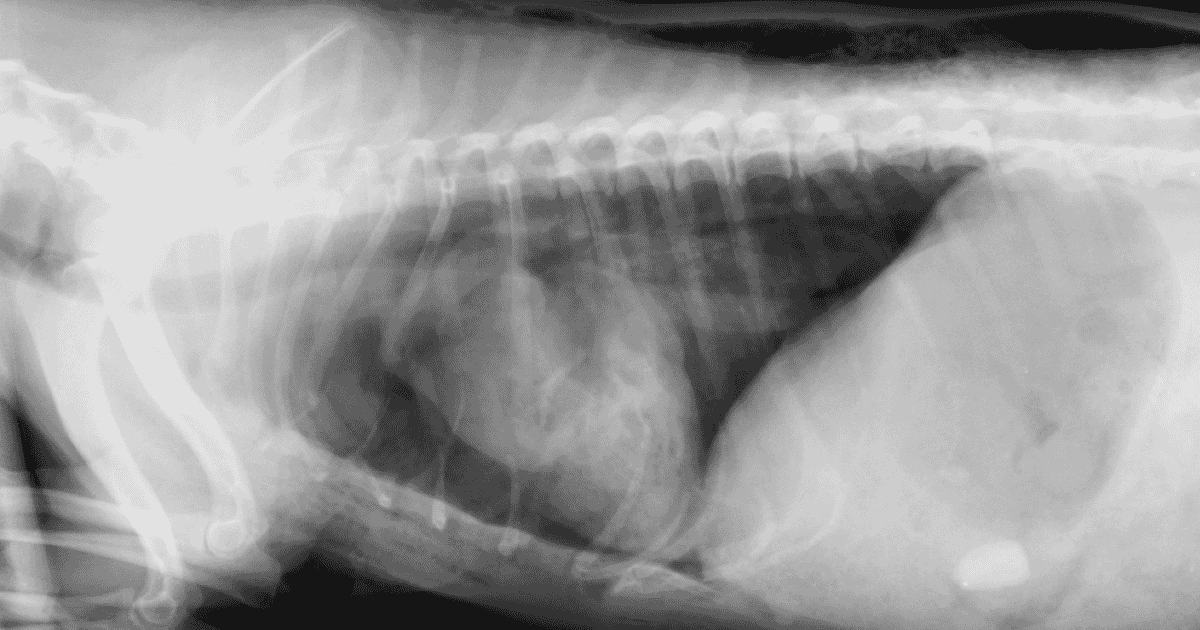

Management Of Thoracic Dog Bite Wounds Veterinary Practice